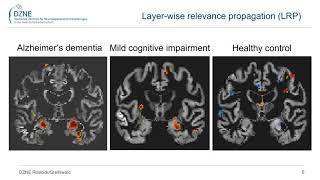

Detect any Landmarks or heritages with CNN Comparison of CNN Visualization Methods to Aid Model Interpretability for Detecting AD in MRI Scans

Comparison of CNN Visualization Methods to Aid Model Interpretability for Detecting AD in MRI Scans Enhancing Cardiac MRI Segmentation via Classifier-Guided Two-Stage Network and All-Slice

Detect any Landmarks or heritages with CNN Comparison of CNN Visualization Methods to Aid Model Interpretability for Detecting AD in MRI Scans

Comparison of CNN Visualization Methods to Aid Model Interpretability for Detecting AD in MRI Scans Enhancing Cardiac MRI Segmentation via Classifier-Guided Two-Stage Network and All-Slice